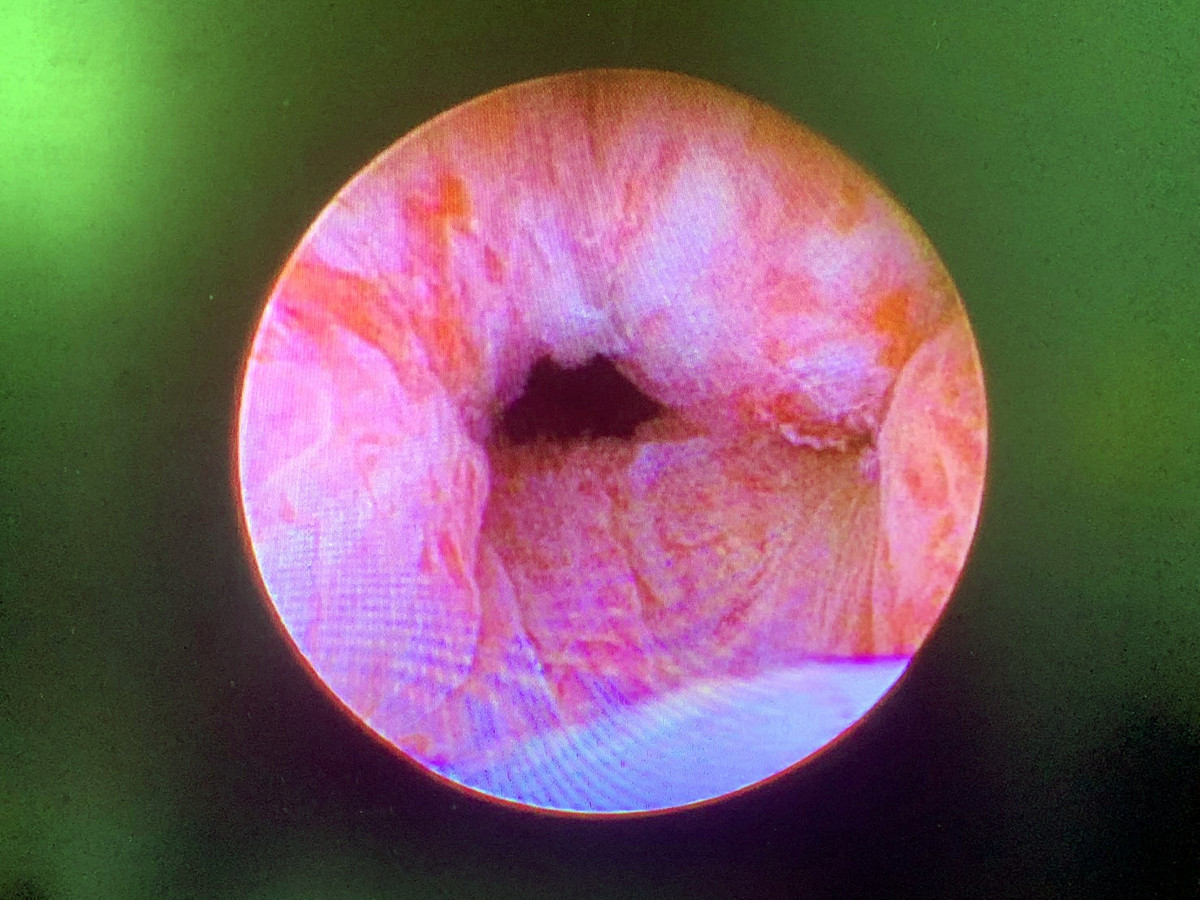

70歲的 H 先生,患有糖尿病跟高血壓,長期解尿速度慢,小便解不乾淨,診斷為攝護腺肥大(大約50cc) ,於門診治療,服用攝護腺放鬆及縮小藥物後,症狀仍未有改善,且藥物副作用使其勃起功能受影響。經醫師評估後接受攝護腺拉開手術(如圖一及圖二),術後小便恢復暢通,勃起功能亦回復,甚至無需再服用任何攝護腺肥大藥物。

「攝護腺拉開手術」是一種微創、相對安全的新選擇。劉家翔主任進一步說明,此手術是經由內視鏡,將鎳鈦合金的釘子植入攝護腺肥大的腺體,造成擠壓進而拉開尿路,後續攝護腺組織會因擠壓造成的缺血產生萎縮,尿路即可長期保持通暢;因為手術過程並無加熱切割或是破壞組織,所以不會造成出血、結疤,也不影響射精與勃起功能。